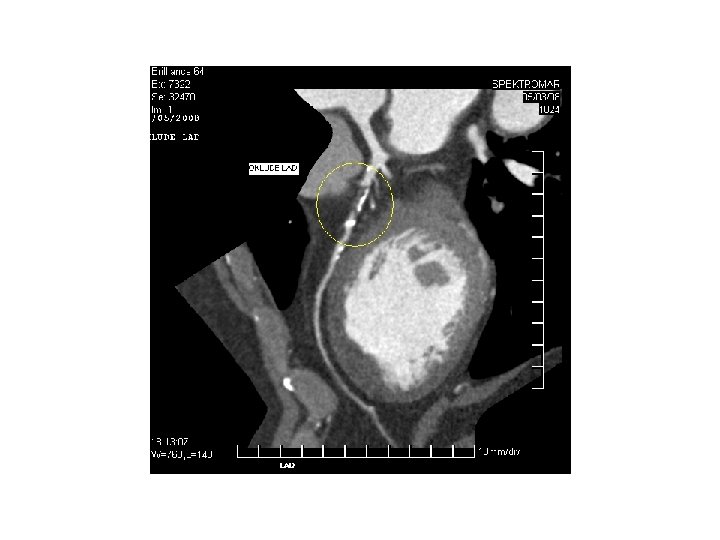

İLİAC PTA STENT